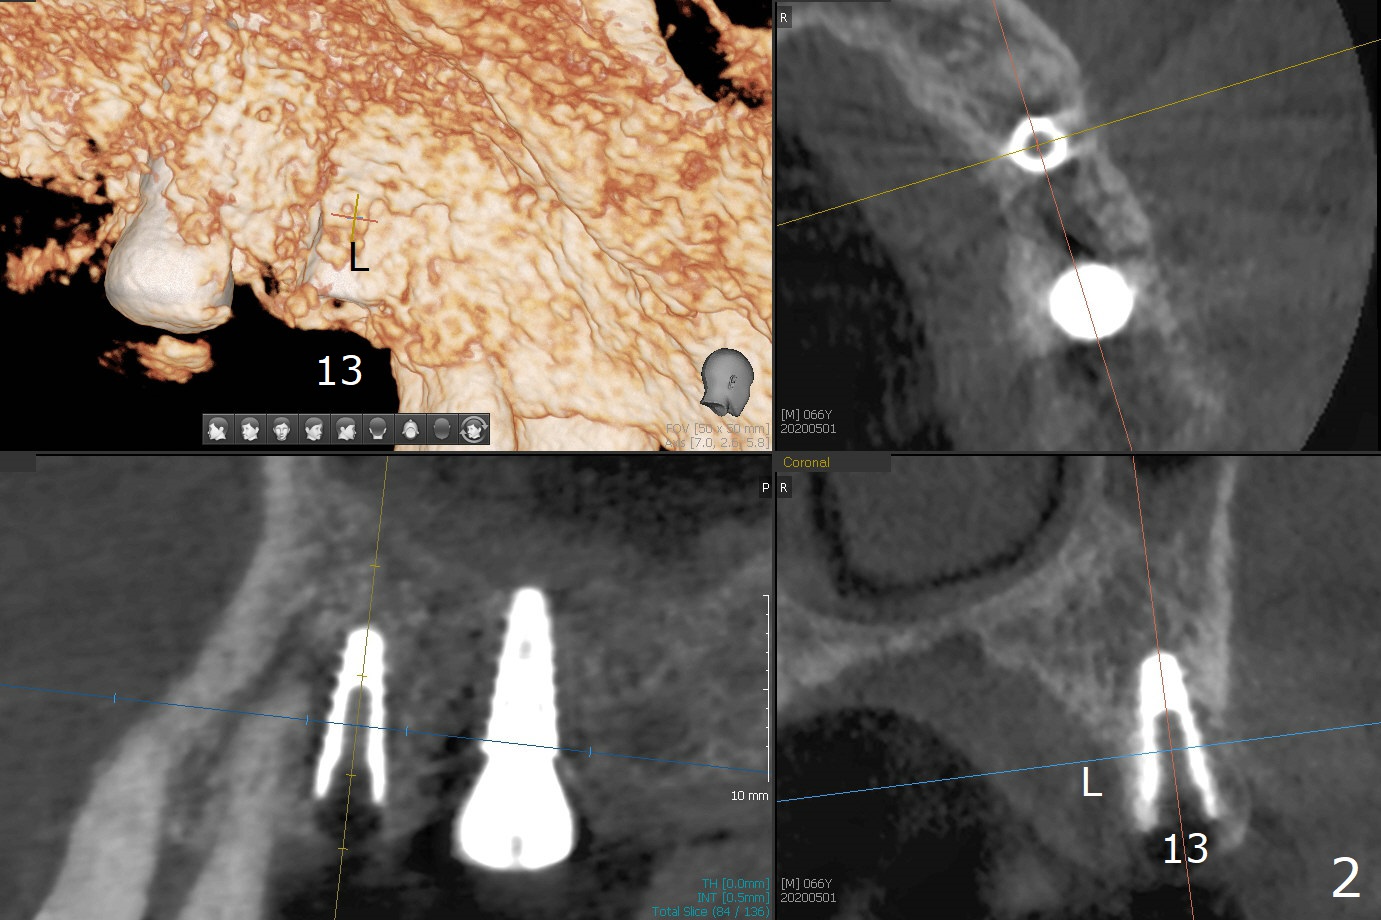

The patient returns for #4 extraction and immediate implant the 1st day clinic reopening after coronavirus lockdown. To reuse autogenous bone for #4 buccal gap closure, delayed implants are also placed at #13 and 14. It is much easier to determine the placement level of the immediate implant (open socket) with guide than that of the delayed ones (flapless) clinically. Immediate postop CT is taken for implant placement level confirmation (Fig.1-3). In fact the autogneous bone is too soft to be packed into #4 socket gaps. It has to be mixed with allograft to be packable. There is oozing when #14 healing abutment is placed. The hemorrhage is severe 4 days postop. The healing abutment is replaced by a healing screw. Hemostasis is achieved when the access is closed with GEM Cap and 4-0 Chromic gut suture. The patient will return for #3 extraction and socket preservation 1 month postop (Fig.4). To prevent postop hemorrhage, a cemented or temporary abutment will be placed at #4 before anesthesia, while .5 or 1.0 cc Augma bone will be placed at #3, covered with collagen plug and acrylic. In fact he cancels the appointment once because of symptom relief and will return 2 months postop. Sticky bone (Fig.5 *) and PRF is used at #3 for hemostasis, while a 5x5.7(3) mm pair (final) abutment is used to hold acrylic dressing in place. The latter remains in place with good oral hygiene 1 month postop (Fig.6 A: abutment). When the acrylic dressing is removed, the socket heals (Fig.7 K: the gingiva between the buccal and palatal sockets when the tooth was removed). The patient returns for impression 4.5 months postop. When the 5x5.7(3) mm abutment at #4 is reseated after cleaning, there is no horizontal gap between the abutment and implant in BW (Fig.8), while there is in PA (Fig.9). When a smaller abutment is seated (Fig.10), there appears to be a horizontal gap, whereas there is no vertical one. The situation is the same with #13 (Fig.11,12). The common denominator is 3.5 mm implant. With suspicion, BW is taken for the implant at #4 immediately before cementation (Fig.13). It appears that the abutment is most likely seated completely. There is no bone loss or screw loosening 4 months post cementation (Fig.14,15). One month later the patient agrees to have 3 lower implants to replace RPD.